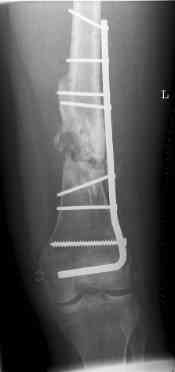

aug 06: blade plate + bone graft

nov 06: revision blade plate

feb 07: retrograde nail + bone graft + BMP

nov 07: persistant non-union distal femur; other fractures healed uneventfully.